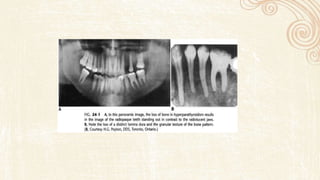

• The lesions are seen as patchy areas of radiolucency which may later coalesce

to form generalized areas of ill-defined radiolucency of the bone

• The lesions are usually bilaterally present

Periapical radiographs of left mandible illustrating multi focal areas of bone destruction

and widening of portions of periodontal ligament space.